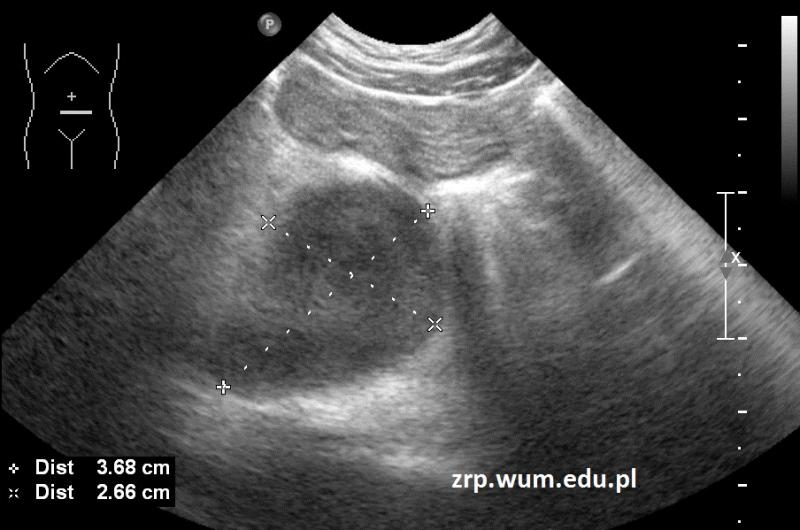

Przypadek 53: 4-letni pacjent obserwowany w kierunku choroby układowej, z obrzękiem i bólem kolana prawego, ze stanami podgorączkowymi utrzymującymi się od miesiąca.

Rozpoznanie: W badaniu USG w śródbrzuszu, pod pępkiem, uwidoczniono dwie hipoechogenne owalne zmiany, o wym. 37x27x22mm i 13x12mm, na tej podstawie wysunięto podejrzenie chłoniaka. Potwierdzono rozpoznanie chłoniaka Burkitta